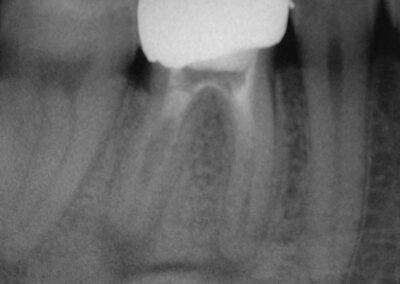

Auf der Basis einer sorgfältigen Evaluation unserer Fälle können wir ganz im Gegensatz dazu aussagen, dass wir in diesen Fällen mit unserem Endodontie-Protokoll eine Quote röntgenologisch knochendichter Ausheilung von sehr nahe an 100% erreichen. Dies gilt auch für bereits wurzelspitzenresezierte Zähne, die exazerbieren und keine Längsfraktur aufweisen.

Wenn es uns gelingt, Zugang zum Knocheninfekt zu schaffen, können wir diesen also ausgesprochen zuverlässig ausheilen. Das ist ja auch kein Wunder. Alles andere wäre vielmehr überraschend. Denn wo keine Bakterien mehr sind, hört eine bakterielle Infektionskrankheit auf zu existieren.

Und zum Abschluss noch eine schöne Doublette:

Galerie: